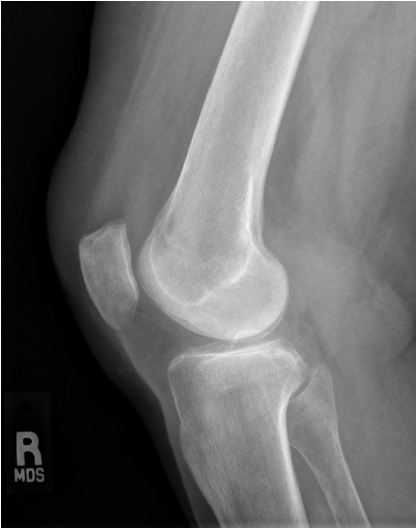

In the mediolateral projection of the knee, which of the following structures are visualized?

A - Superimposed medial and lateral femoral condyles

B - Intercondylar eminence

C - Medial malleolus

D - Fibular head

E - Patellofemoral joint space

F - Intercondylar fossa

G - Lateral malleolus

H - Infrapatellar fat pad region

A

The answers are A, D, E, and H.

In the mediolateral projection of the knee, the femoral condyles should be superimposed (A). Proper CR angulation and elimination of tilt can demonstrate the intercondylar eminence, seen here superimposed on the femoral condyles (B), and lack of rotation will be evident by visualization of the patellofemoral joint space (E). The fibular head (D) is located on the proximal fibula and will be projected partially superimposed by the tibia. Lastly, soft tissue detail, such as the fat pad anterior to the knee joint (infrapatellar fat pad), will be seen